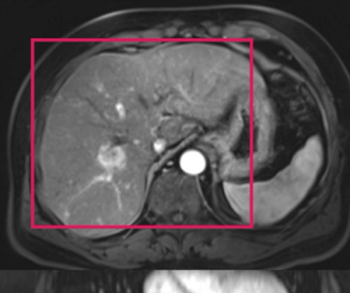

Noting that the machine learning model incorporating magnetic resonance imaging (MRI) had a higher mean area under the curve (AUC) than a model based solely on clinical features for predicting hepatocellular carcinoma recurrence, researchers said the study findings could have implications for refining liver transplant criteria.